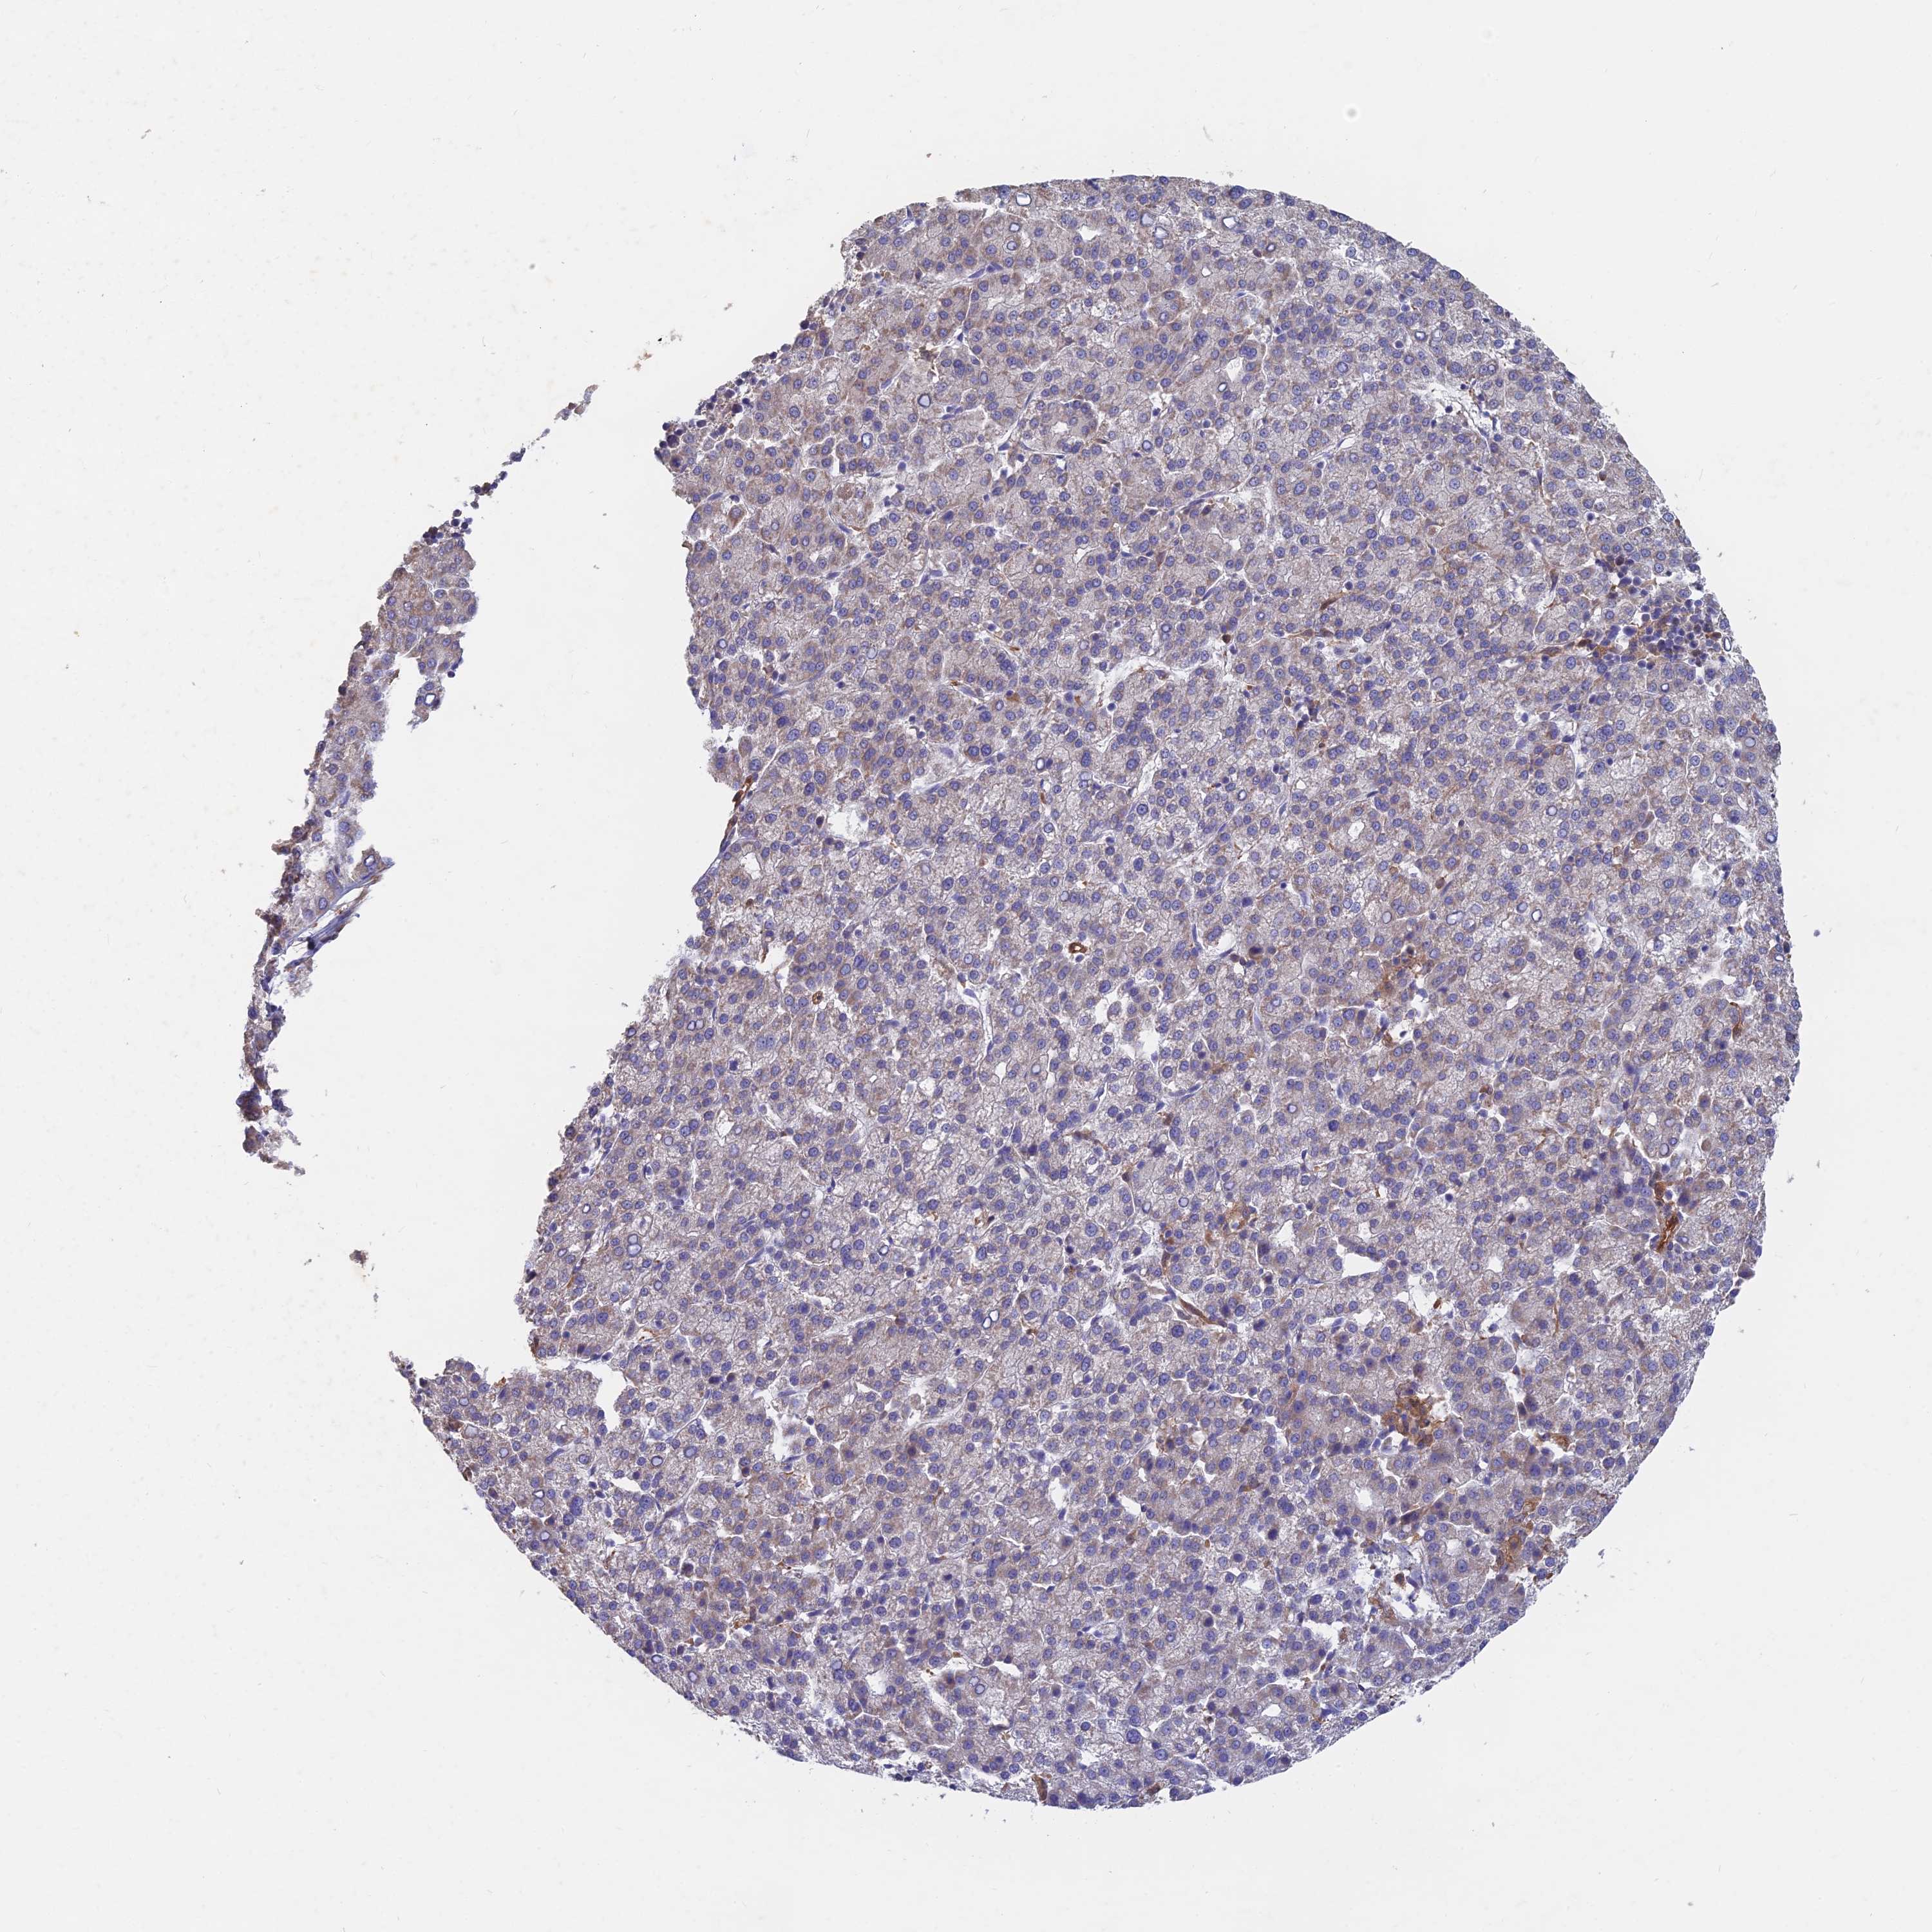

LIVER CANCER - Protein expressioni

A mouse-over function shows sample information and annotation data. Click on an image to view it in a full screen mode. Samples can be filtered based on level of antibody staining by selecting one or several of the following categories: high, medium, low and not detected. The assay and annotation is described here.

Note that samples used for immunohistochemistry by the Human Protein Atlas do not correspond to samples in the TCGA dataset.

Antibody stainingi

Antibody staining in the annotated cell types in the current human tissue is reported as not detected, low, medium, or high, based on conventional immunohistochemistry profiling in selected tissues. This score is based on the combination of the staining intensity and fraction of stained cells.

Each image is clickable and will lead to virtual microscopy that enables deeper exploration of all samples and also displays staining intensity scores, fraction scores and subcellular localization as well as patient and tissue information for each sample.

Antibody HPA042677

Staining

High

Medium

Low

Not detected

Intensity

Strong

Moderate

Weak

Negative

Quantity

>75%

75%-25%

<25%

None

Location

Nuclear

Cytoplasmic/membranous

Cytoplasmic/membranous,nuclear

Cholangiocarcinoma

Carcinoma, Hepatocellular, NOS